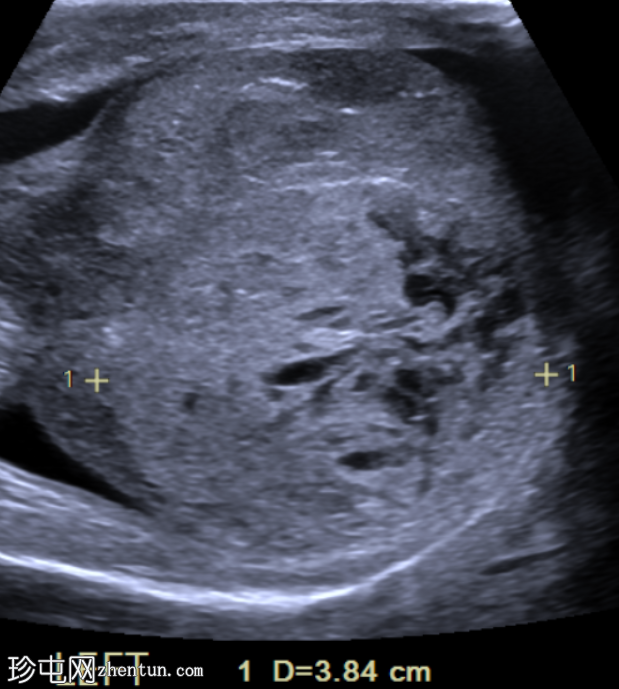

左侧睾丸可见边界不清的肿块,实质回声不均匀,并可见囊性区域。彩色多普勒超声显示血流信号增多。未见钙化。

肉眼观察结果:左侧睾丸重 80 克,大小为 65 x 60 x 45 毫米。肿瘤呈灰褐色,最大可评估直径为 61 毫米。未见鞘膜或精索受侵犯的肉眼证据。